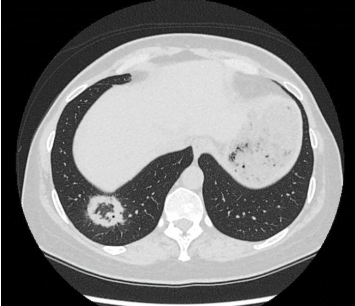

Revers halo-tegn (også kaldet atoll-tegn) beskriver et infiltrat med central matglastegning og ringformet konsolidering, som ses hos ca. 20% af patienter med OP, men er et fund med høj specificitet.

Figur 1 og 2 viser eksempel på hhv. revers halo-tegn og subpleurale konsolideringer på HRCT.

Figur 1: Aksialt HRCT-billede med revers halo-tegn (’atoll tegn’) i højre underlap præsenteret ved ringformet konsolidering med central matglastegning.